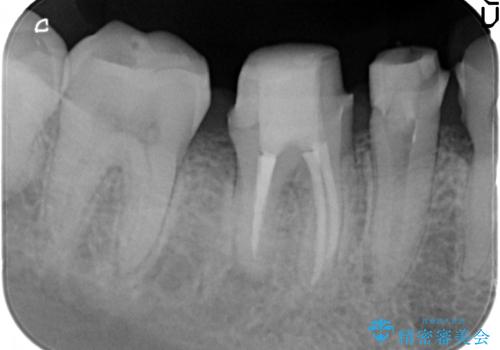

- 放置してしまった虫歯治療を希望され来院されました。

虫歯を徹底的に除去したのち、長期的に安定し審美的なジルコニアクラウンで機能回復を図ります。